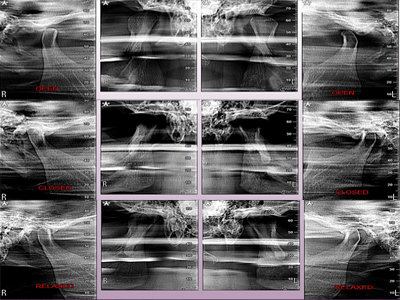

3D Imaging with Field of View sizes available in:

We practice the ALARA principle; (As low as Reasonably Achievable) all scans are restricted to the “Field of View” of your dentist’s prescription. It is taken using (1) pulsed x-ray exposure protocols, (2) real-time-automatic exposure control of the x-ray dose based on the patient’s actual bone density & (3) high resolution digital x-ray image sensors. These factors lead to a significant reduction in x-ray exposure equivalent to only 10% of the x-ray dose of a medical CT-Scan.

The aforementioned technology is inherent in the “myRay X9 CBCT Scan” that we use. myRay X9 is an Italian-made Oral Maxillofacial CT-Scan, certified compliant by European, Japan, USA and other international authorities in radiation safety.